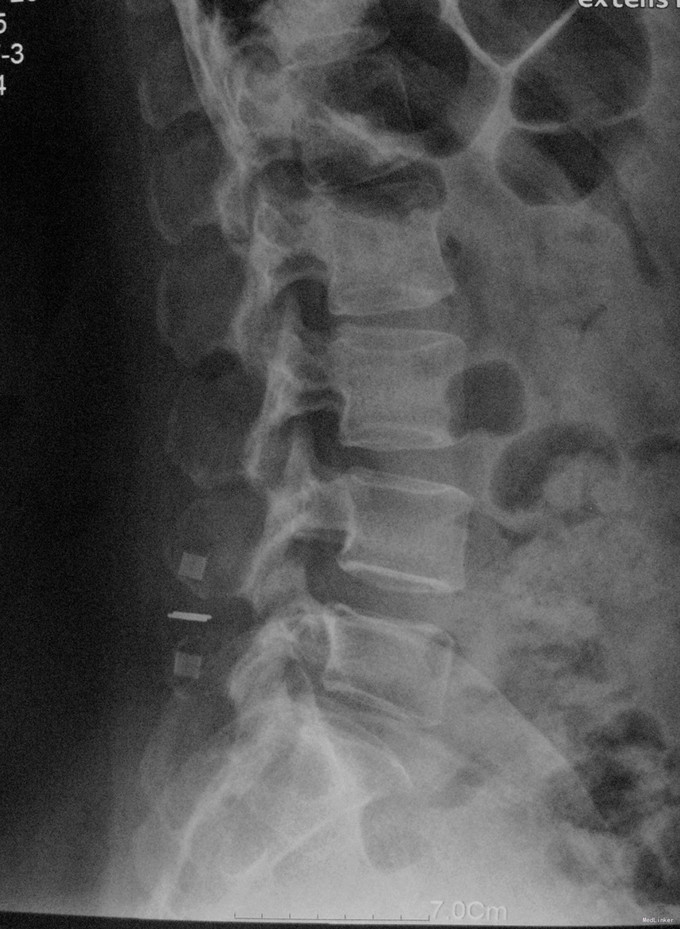

查体:脊柱生理弯曲存在,腰椎活动受限,L4/L5棘突压痛叩痛,叩击痛。双侧直腿抬高试验(-)。双下肢皮肤感觉正常,双侧髂腰肌、股四头肌、双侧胫前肌、踇背伸肌肌力Ⅳ级,腹壁反射、肛门反射正常,两侧膝正常,双侧踝反射未引出。双侧Babinski征(-),双侧皮温及色泽正常,双侧足背动脉搏动良好。 辅助检查:X光片示:动力位片显示腰椎4/5椎间失稳。MRI检查显示:腰4/5椎间盘突出,黄韧带肥厚致椎管狭窄,相应节段硬膜囊受压改变。

诊断:腰4/5椎管狭窄并失稳症。 治疗:给予行后路腰4/5右侧椎板间开窗减压椎间盘摘除并肥厚黄韧带切除+棘突间wallis固定术。